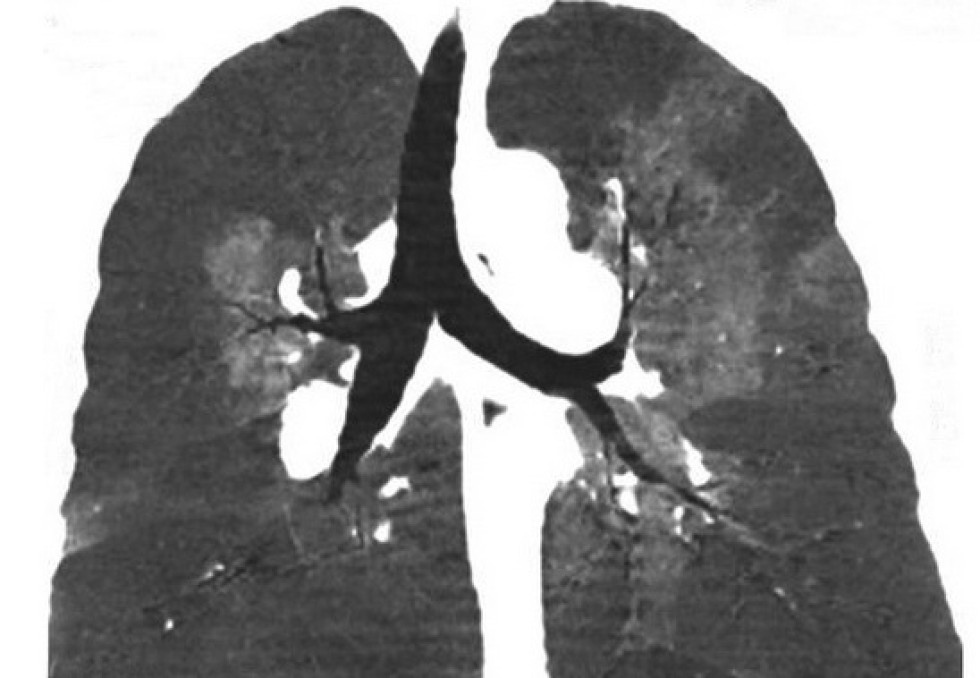

Leurs services d’urgences et de médecine interne et vasculaire proposent, en effet, depuis peu aux patients venant consulter pour une maladie thrombo-embolique veineuse (MTEV) non grave de rentrer chez eux avec un traitement ad hoc et un rendez-vous de suivi à J+3. "On croit encore que toutes les phlébites ou les embolies pulmonaires sont des pathologies graves nécessitant une hospitalisation et une surveillance importante. En fait, 3 à 4 fois sur 10, l’hospitalisation peut être évitée puisqu’il s’agit avant tout d’administrer un traitement anticoagulant par voie orale. Il est de mieux en mieux toléré et efficace en quelques heures", explique Hélène Desmur-Clavel, médecin interniste et vasculaire à l’origine de la prise en charge. "Après validation du degré de gravité de la MTEV (score clinicobiologique), le patient rentre chez lui avec un courrier explicatif et un traitement anticoagulant et peut à tout moment contacter l’hôpital s’il constate un problème. Il est systématiquement revu à J+3 pour un 'debriefing' et d’autres consultations sont envisagées à M+1, +6...", complète-t-elle. Pour valider cette prise en charge, une phase test a été mise en place à l’hôpital Edouard-Herriot. Sur la première année, 36 patients (24 hommes ; âge moyen 53,3 ans) ont bénéficié de cette prise en charge, ce qui représente 18% des MTEV accueillis aux urgences. Sur ces 36 patients, ont été diagnostiqués : 16 embolies pulmonaires, et 24 phlébites. Deux patients n’ont pas suivi la filière en totalité. "Le bilan à un an est globalement positif puisque qu’il n’y a eu aucune post-hospitalisation et qu’aucune hémorragie n’a été observée", assurent les HCL. Les patients ont été globalement satisfaits. A terme, on estime que la prise en charge à domicile pourrait être appliquée dans 30 à 40%. Cela concernerait environ 700 patients /an.